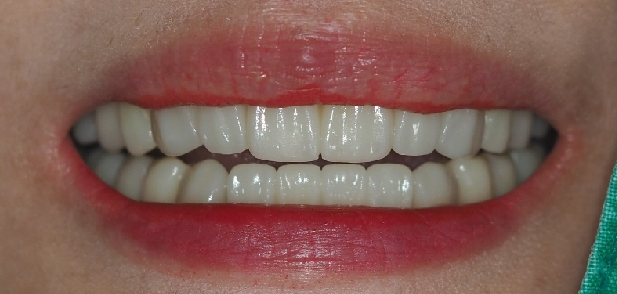

최종 치료 완료된 구강 모습입니다. 앞전의 구강 사진과 비교해보시면 자연스러운 치아의 모습이 완성된것을 확인 할수 있습니다.

전체 최종 치료 기간은 9개월 소요 되었습니다

환자분은 사람들과 많이 대면하고 이야기 해야 하는 서비스 직이라 그때마다 불편하셨는데

지금은 너무 편하게 지내고 있기도 하고 치료과정과 결과도 너무 만족 스러워 하셔서

저희가 너무 뿌듯할 따름입니다.